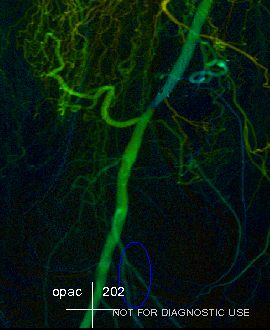

彩色血流编码iFlow基于DSA造影序列一键式生成彩色编码图像,直观且量化的显示血流动力学信息,如造影剂达峰时间等。通过血流达峰时间定量分析对术前术后疗效进行评估。